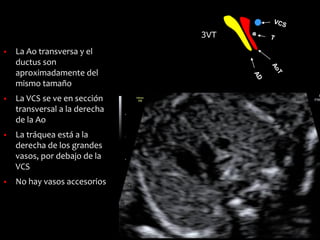

3VT

Tres vasos-tráquea

Paralelo al 3V y más

cefálico

▪ La Ao transversa y el

ductus son

aproximadamente del

mismo tamaño

▪ La VCS se ve en sección

transversal a la derecha

de la Ao

▪ La tráquea está a la

derecha de los grandes

vasos, por debajo de la

VCS

▪ No hay vasos accesorios